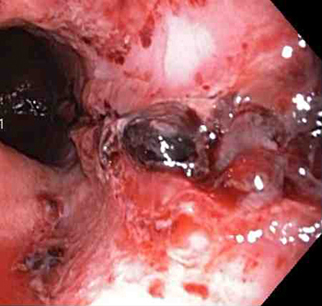

A terapia por injeção é comumente usada no tratamento da ulceração causadora de hemorragia digestiva alta, em combinação com terapia térmica ou mecânica. Seu papel no tratamento do sangramento por laceração de Mallory-Weiss foi estudado em uma pequena série.[71][72] Geralmente, o agente mais comumente usado é uma injeção de adrenalina; esse agente interrompe ou reduz a velocidade do sangramento por vasoconstrição ou tamponamento. É injetada ao redor ou dentro do ponto de sangramento. Agentes esclerosantes, como etanolamina e álcool, têm sido descritos na literatura; no entanto, eles são raramente usados na prática.[73][Figure caption and citation for the preceding image starts]: a laceração com sangramento ativo aparece como um defeito longitudinal vermelho com mucosa circundante normalDo acervo de Juan Carlos Munoz, MD, University of Florida [Citation ends].